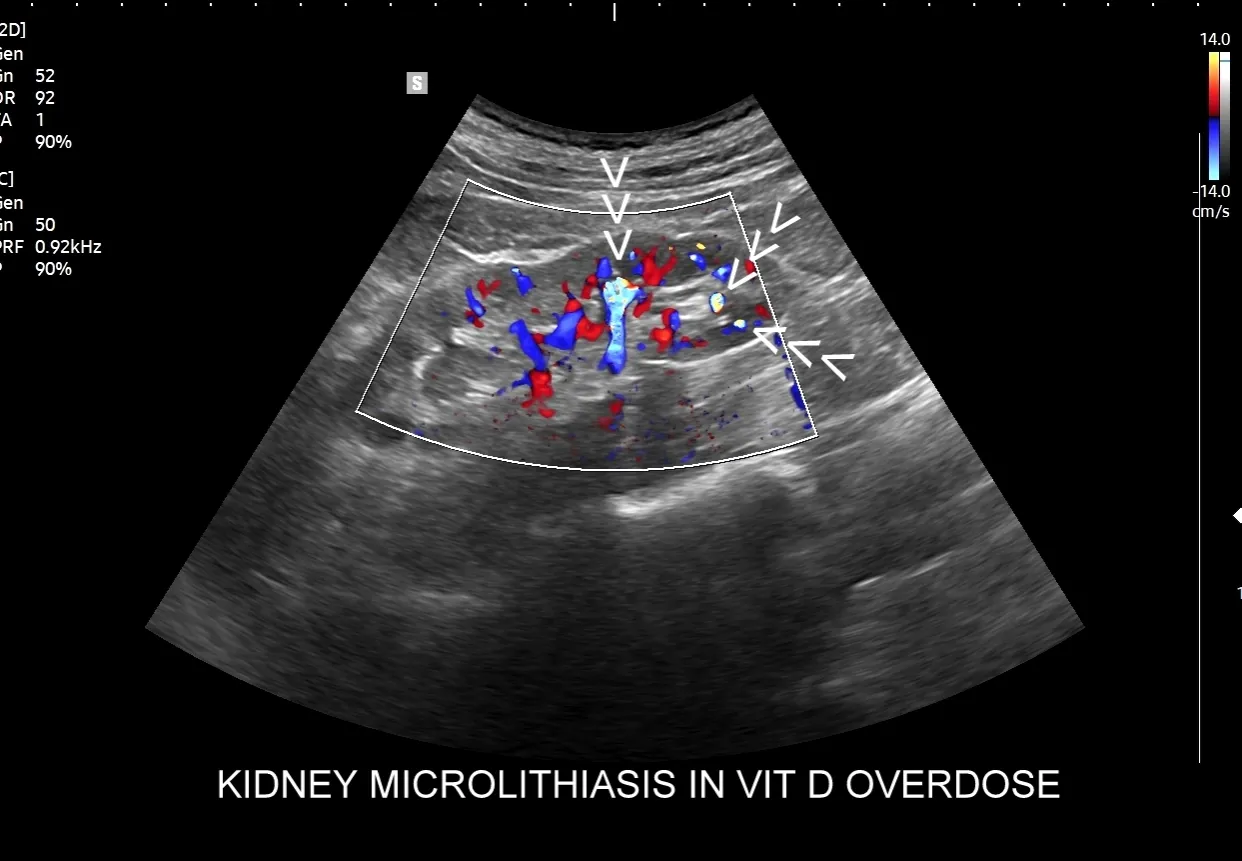

USG układu moczowego jest zazwyczaj pierwszym badaniem obrazowym, które zleca się przy podejrzeniu kamicy nerkowej, szczególnie w przypadku kolki nerkowej. To badanie jest szybkie, nieinwazyjne i całkowicie bezpieczne, ponieważ nie wykorzystuje promieniowania jonizującego. Dzięki temu jest preferowaną metodą diagnostyczną u dzieci i kobiet w ciąży. USG pozwala na uwidocznienie kamieni o wielkości powyżej 3-4 mm, określenie ich lokalizacji w nerkach i górnych drogach moczowych, a co najważniejsze sprawdzenie, czy nie doszło do zastoju moczu, czyli wodonercza. Wodonercze jest sygnałem, że kamień blokuje odpływ moczu, co wymaga szybkiej interwencji.